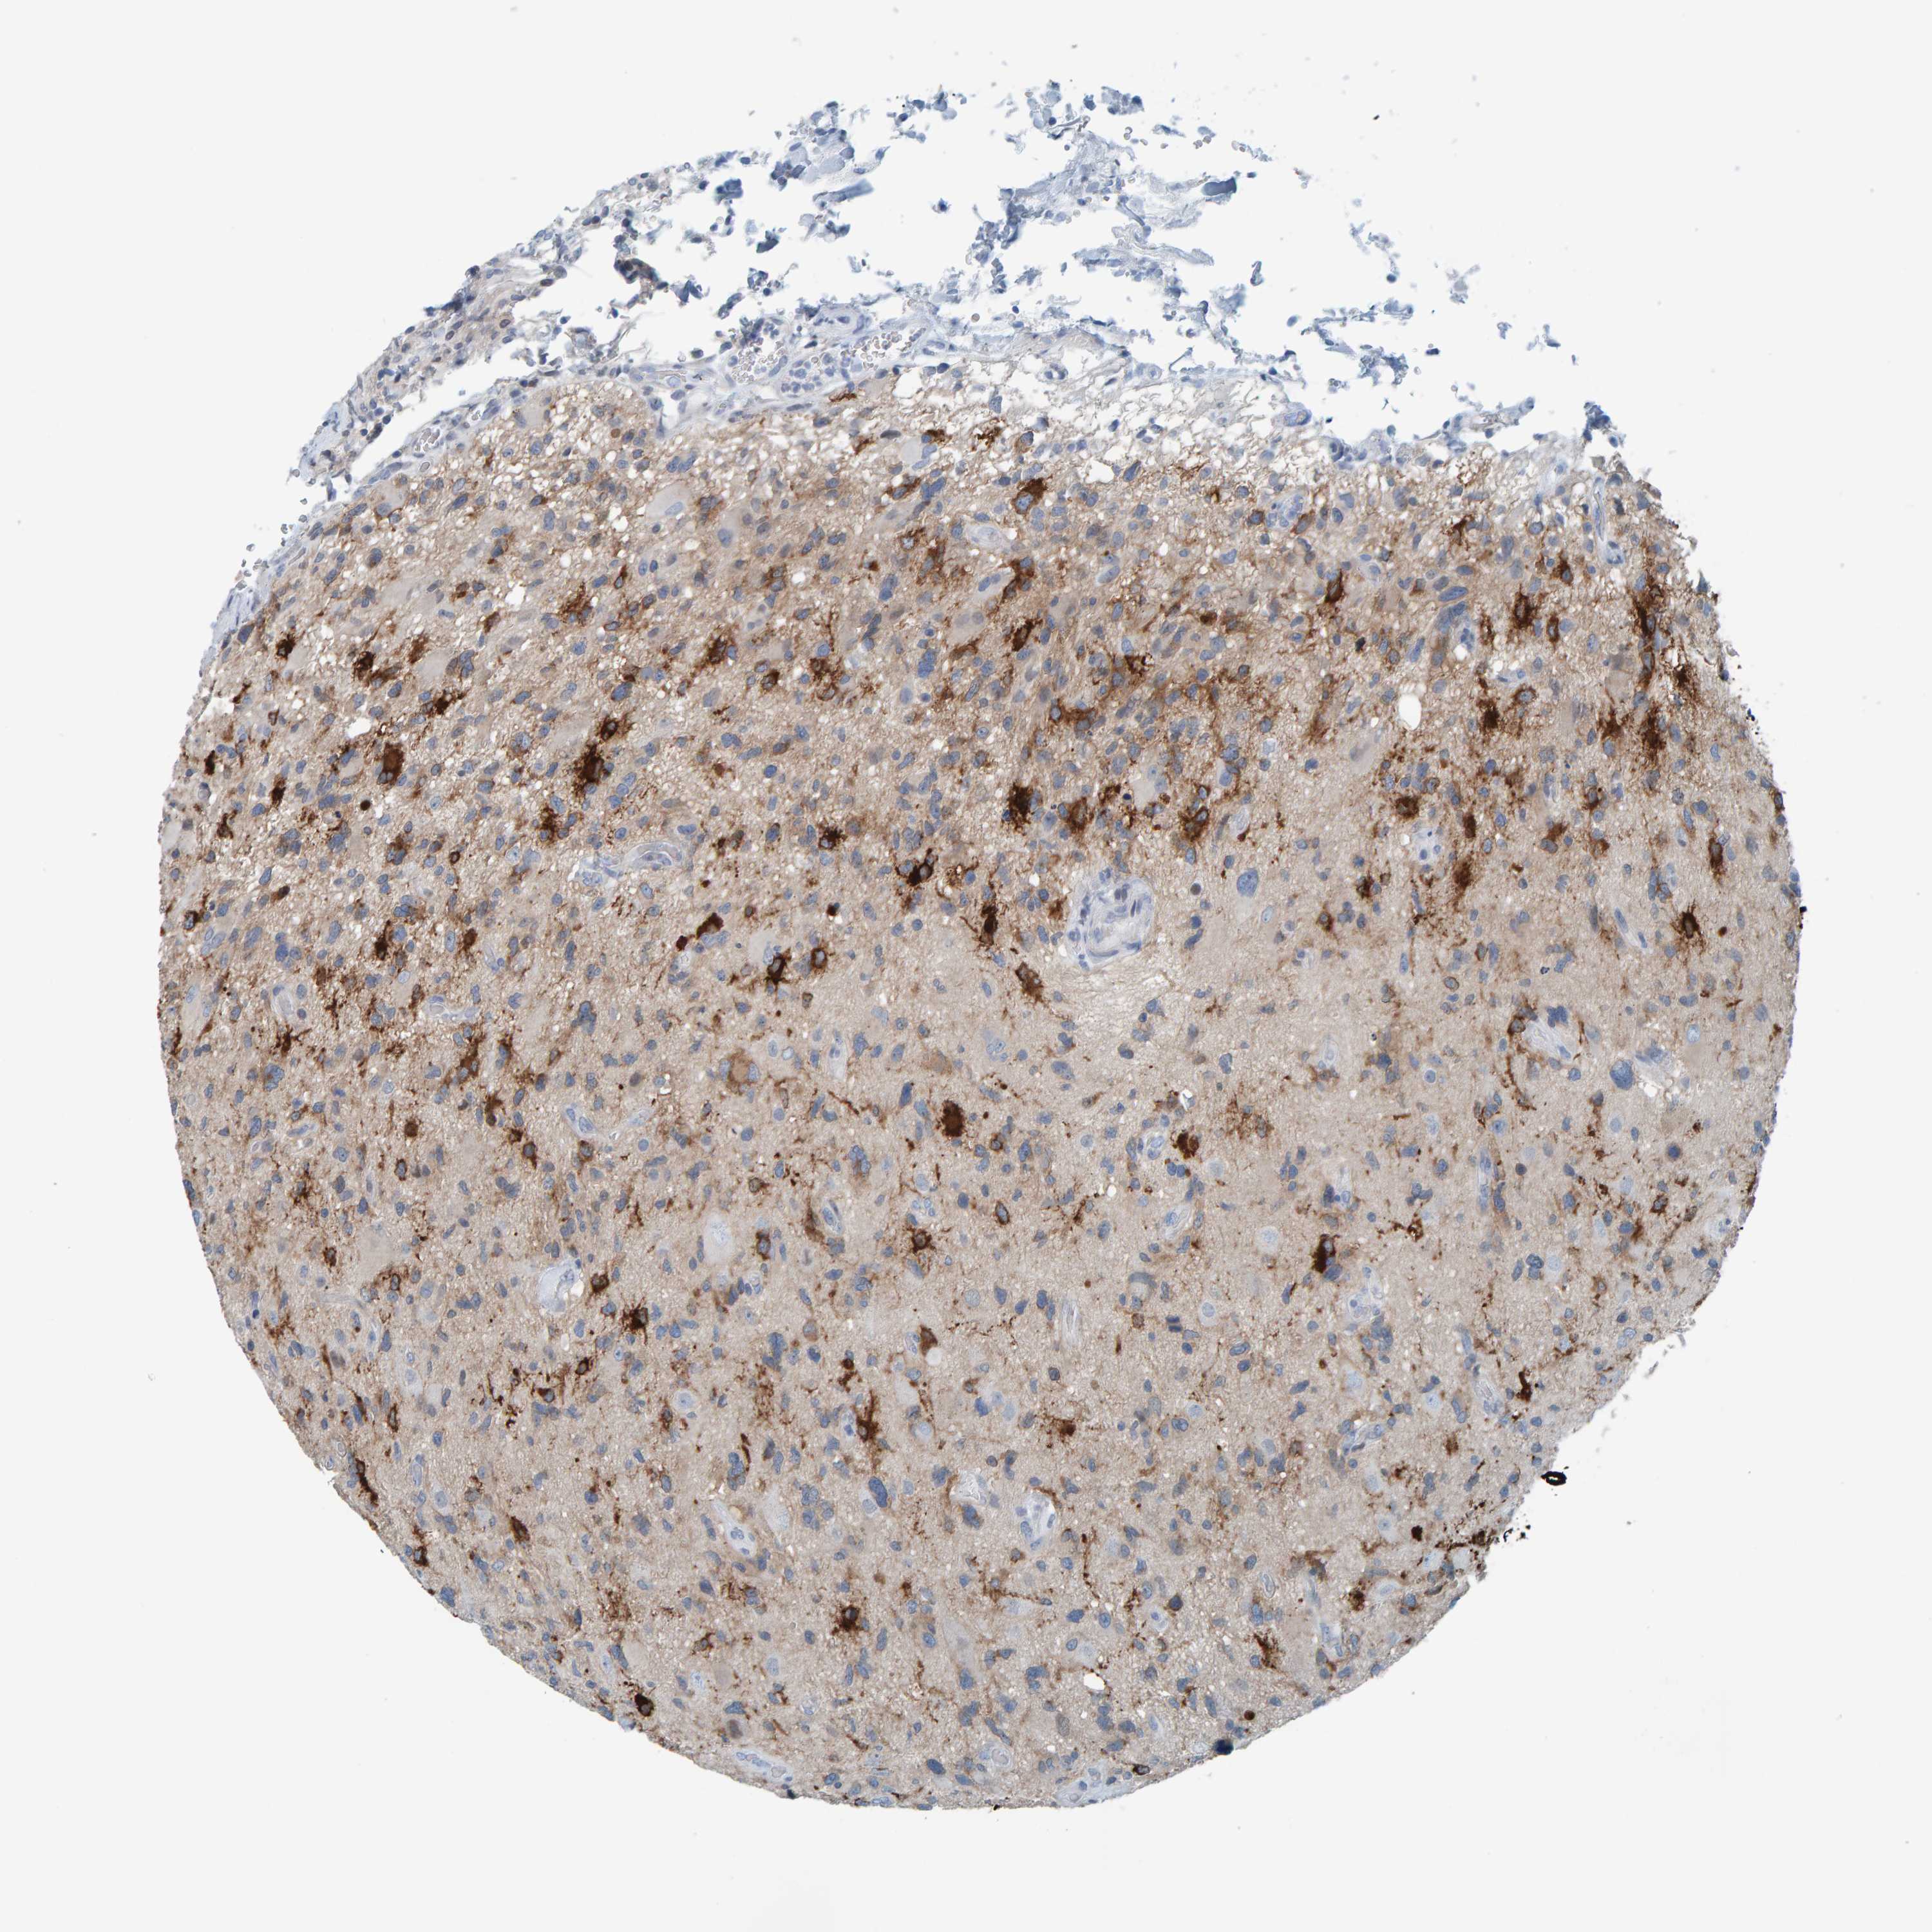

GLIOMA - Protein expressioni

A mouse-over function shows sample information and annotation data. Click on an image to view it in a full screen mode. Samples can be filtered based on level of antibody staining by selecting one or several of the following categories: high, medium, low and not detected. The assay and annotation is described here.

Note that samples used for immunohistochemistry by the Human Protein Atlas do not correspond to samples in the TCGA dataset.

Antibody stainingi

Antibody staining in the annotated cell types in the current human tissue is reported as not detected, low, medium, or high, based on conventional immunohistochemistry profiling in selected tissues. This score is based on the combination of the staining intensity and fraction of stained cells.

Each image is clickable and will lead to virtual microscopy that enables deeper exploration of all samples and also displays staining intensity scores, fraction scores and subcellular localization as well as patient and tissue information for each sample.

HPA023266

HPA023278

HPA023280

HPA023338

CAB002672

Glioma, malignant, High grade

Glioma, malignant, Low grade